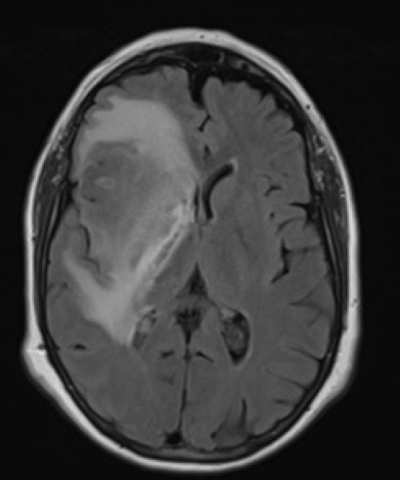

- Tumore und Zysten: Die MRT Kopf kann sowohl gutartige als auch bösartige Tumore im Gehirn erkennen. Sie kann auch bei der Identifizierung von Zysten und anderen strukturellen Anomalien helfen.

Hirntumor in der MRT